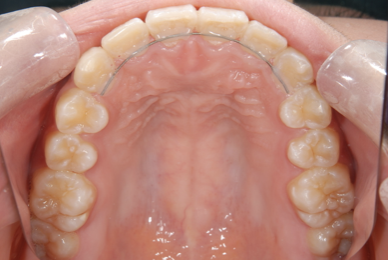

透明なマウスピース型のリテーナー

リテーナーの場合には透明なマウスピース型を使用する場合もあれば、ワイヤーとレジンで作られたプレート型を使用する場合もあります。